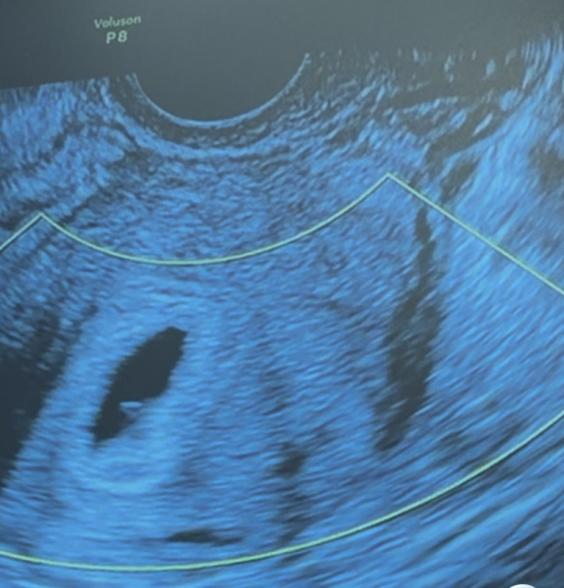

添付した写真の胎嚢の右下あたりにある白いものは卵黄嚢の可能性はありそうでしょうか。

そうですね。お写真からですと、なかなかはっきりとしたことは明言できませんが、いずれにしても、胎嚢の中に何かが写っているということは明確なので、それがもしかしたら卵黄嚢、または胎芽なのかもしれませんね。